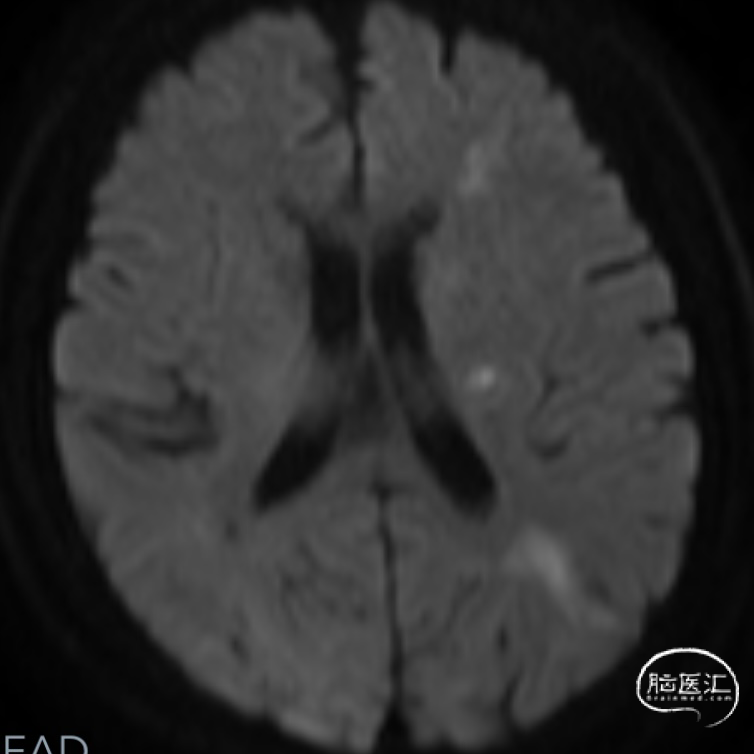

➤2024.3.20 头颅MRI

左侧基底节区/侧脑室旁及额顶枕叶急性期脑梗死。

➤2024.3.20 CTA

左侧大脑中动脉M1段起始部重度狭窄。